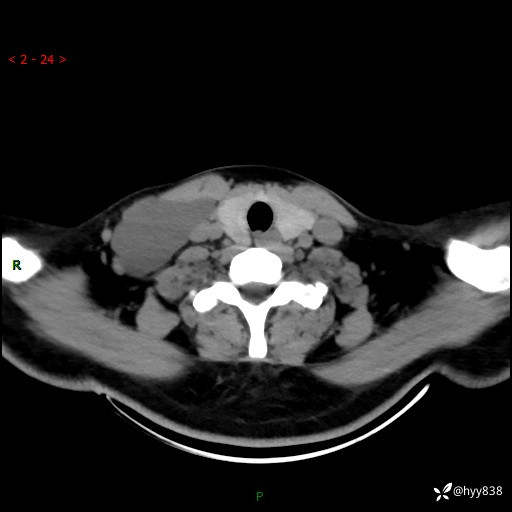

辅助检查:CT

颈部CT平扫

增强动脉期+静脉期